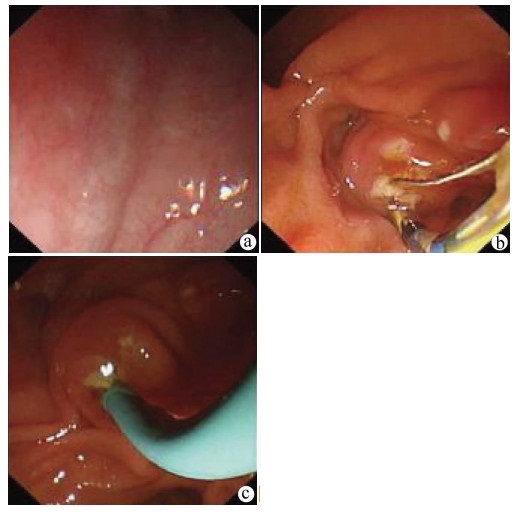

门静脉性胆道病1例报告

姜朋, 王树鹏, 刘亚辉

2022, 38(2): 430-432. DOI: 10.3969/j.issn.1001-5256.2022.02.034

摘要(724) HTML (240) PDF (2686KB)(54)

摘要: